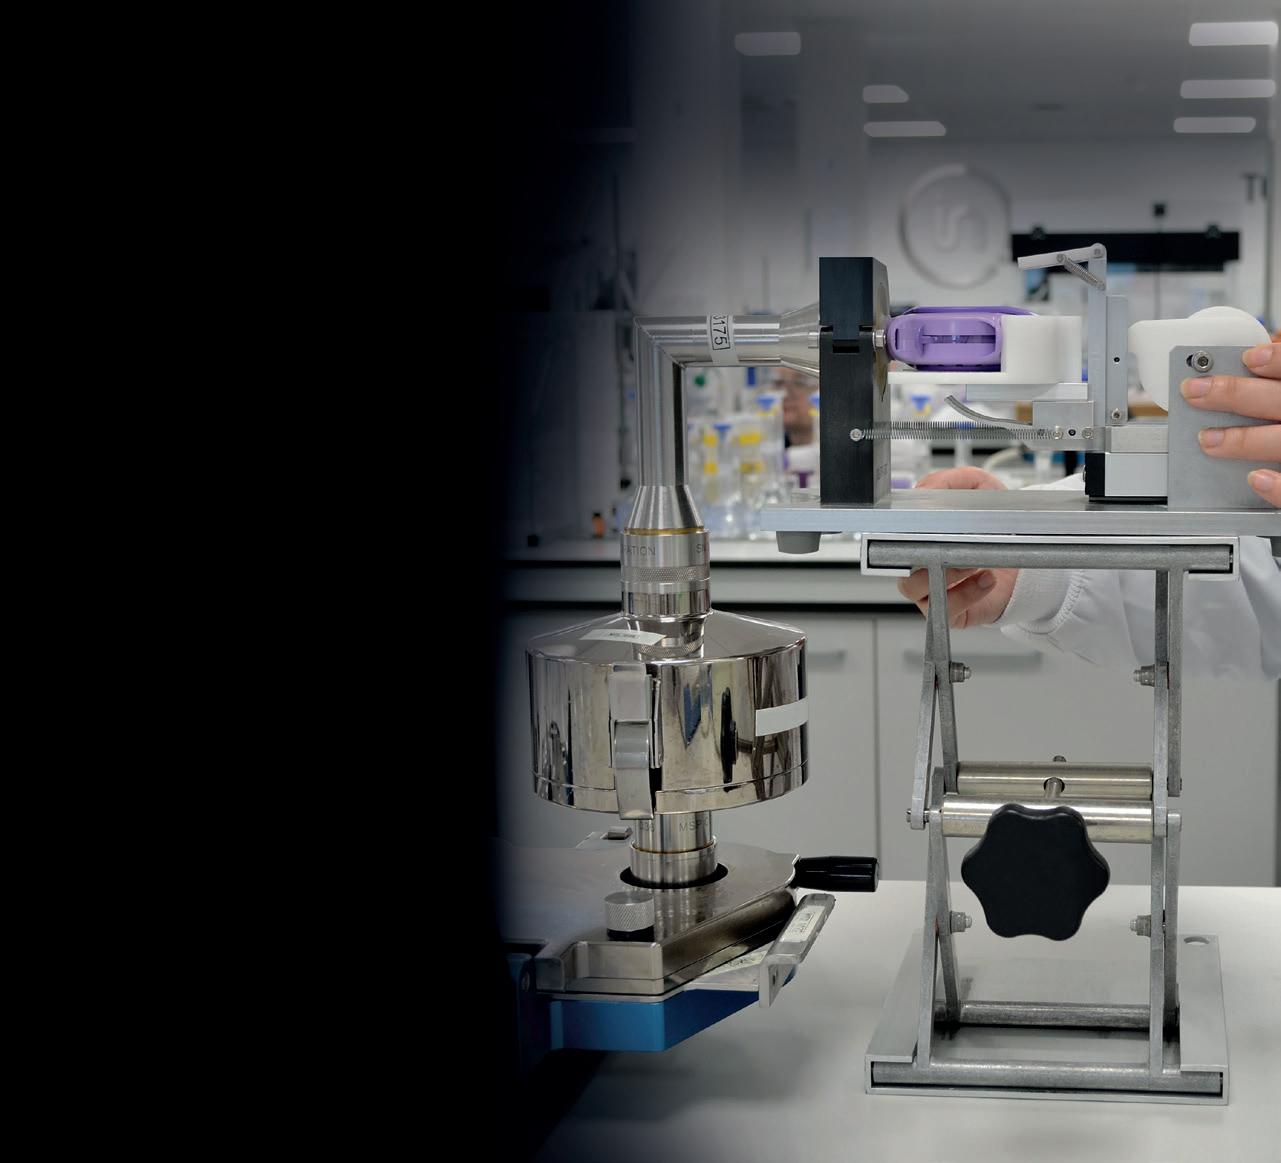

In this article, Gesa Bräunlich, Portfolio Manager eFlow, and Michael Hahn, Vice-President eFlow Partnering & Strategy, both at PARI Pharma, discuss the company’s new eFlow integrated nebuliser.

To maximise the delivered dose, PARI has developed a new breath-triggered nebuliser platform based on the proven eFlow technology with its actively vibrating laser-drilled membrane. The applied trigger algorithm enables delivered dose rates of up to 95%.

With the development of the new eFlow Integrated nebuliser, PARI has implemented an innovative breath-guiding approach and a novel nebuliser platform that supports and guides the patient to inhale slowly and deeply. Three factors have been successfully combined to optimise the breathing pattern accordingly (Figure 1):

First, and most importantly, a unique built-in flow resistance limits the peak inspiratory flow. While flow resistance is higher during inhalation to limit flow rates, it is reduced during exhalation to allow optimal work of breathing and tolerability. This is the result of the specific geometry of an innovative built-in resistance termed fluidic diode. The overall aim is to limit patients’ inspiratory flow, as this helps increase lung deposition and reduce nebulisation time.

The second element to guide patients’ breathing patterns is the user interface on the device. By providing intuitive instructions directly via an illuminated mouthpiece assembly and a vibrating controller, PARI’s new eFlow integrated nebuliser platform effectively trains the patient on the correct breathing pattern during inhalation. A pressure sensor collects real-time data from the inspiratory flow, translating this information into haptic and visual signals that inform the user on whether or not the inhalation is optimal (Figure 2).

The novel nebuliser platform optimises drug delivery with an innovative breathguiding approach. With its patient-centric approach, PARI has made significant advances in optimising the device platform and the entire patient experience to drive adherence and improve performance and clinical use – factors that can translate into clinical success. Beyond this innovative product design, the well-established eFlow aerosol generator, which is a core component, is produced on proven commercial-scale production equipment in two independent manufacturing sites. With the new eFlow Integrated nebuliser, PARI has achieved a high level of integration – the successful blend of:

The new eFlow Integrated nebuliser is still under final development, while it has already confirmed expectations during the first in vitro studies with innovative drug products.